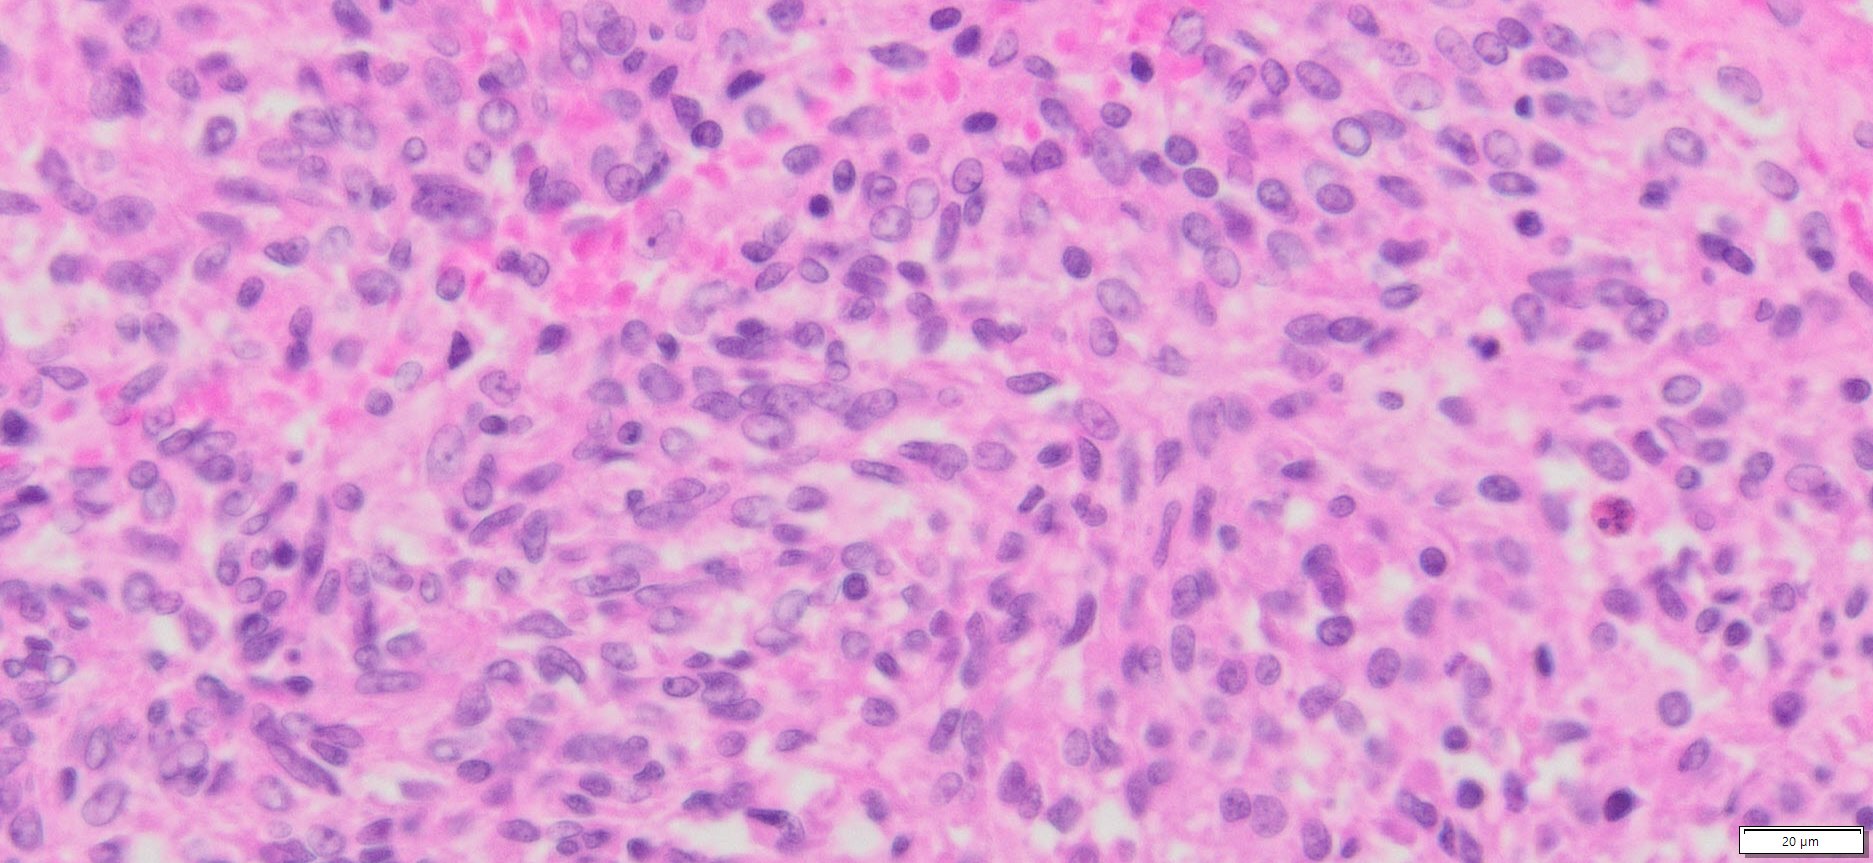

Description

| Organ& Tissue | Pathology Diagnosis | Gender/Age | % Tumor Area | Grade | TMN Stage | IHC Data |

| Human liver | Liver metastases from human gastric stromal tumor | Male/54 | 45% | II | pT4pNxpM1 | NA |